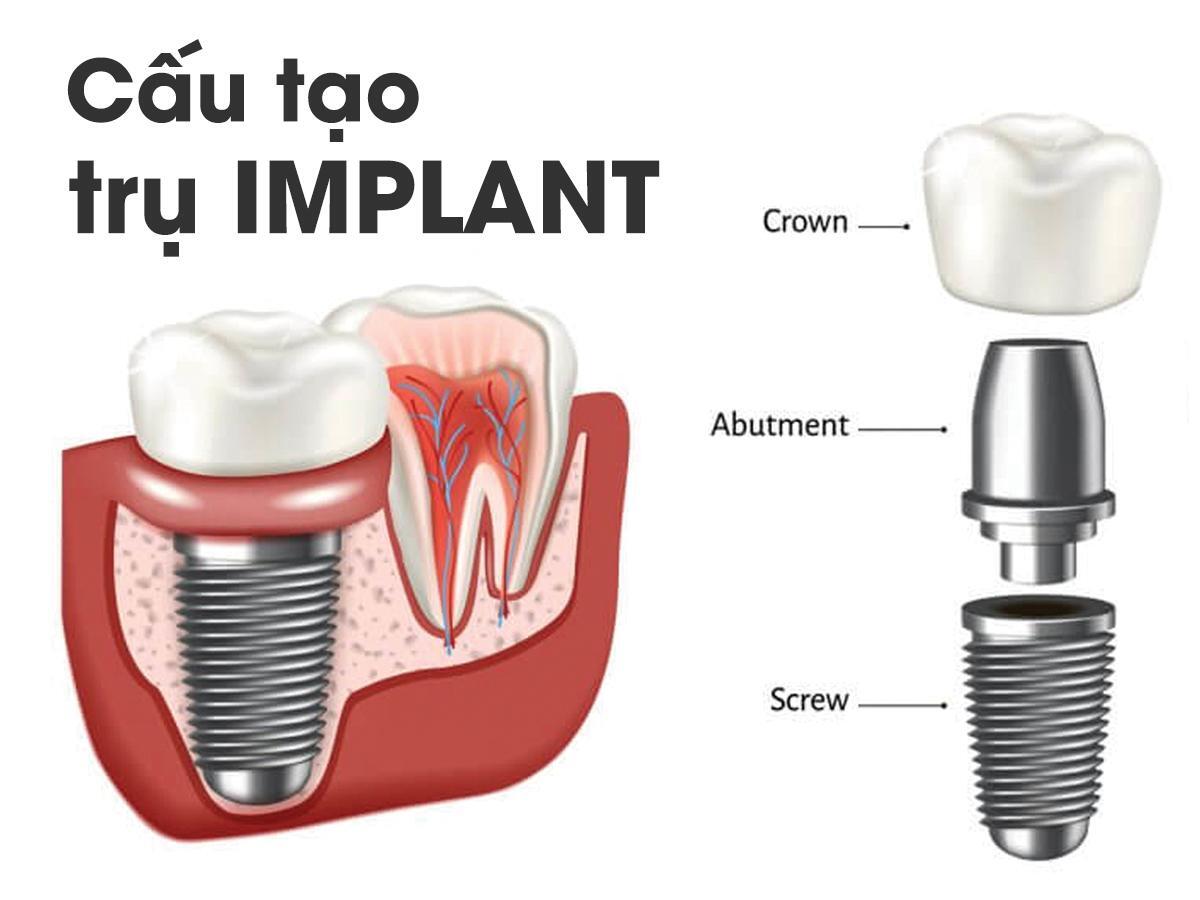

Implant là gì ? Chúng có cấu tạo như thế nào?

Trụ Implant nha khoa là trụ được làm từ Titanium siêu bền, đóng vai trò như chân răng nhân tạo. Trụ này được cấy ghép trực tiếp vào xương hàm để thay thế chân răng đã mất và hỗ trợ mão sứ phục hình thân răng, giúp khôi phục chức năng và thẩm mỹ cho răng. Với độ tương thích sinh học cao, răng Implant giúp cải thiện khả năng ăn nhai, bảo vệ cấu trúc xương hàm, đồng thời mang lại vẻ đẹp tự nhiên, bền vững.

Cấu tạo của một răng Implant bao gồm 3 phần chính:

- Trụ Titanium (Implant): Trụ này có hình dáng giống chân răng thật, được cấy trực tiếp vào xương hàm. Bề mặt trụ có các vòng xoắn giúp trụ tích hợp nhanh vào xương, đảm bảo tính ổn định.

- Khớp nối Abutment: Phần kết nối giữa trụ Titanium và mão răng sứ. Abutment có thể được làm từ kim loại hoặc sứ, đóng vai trò như cùi răng, hỗ trợ việc gắn mão răng.

- Mão răng sứ: Là phần răng giả nằm trên khớp nối, thường làm từ sứ với màu sắc, hình dạng và chức năng giống như răng thật, giúp khôi phục khả năng ăn nhai và thẩm mỹ.